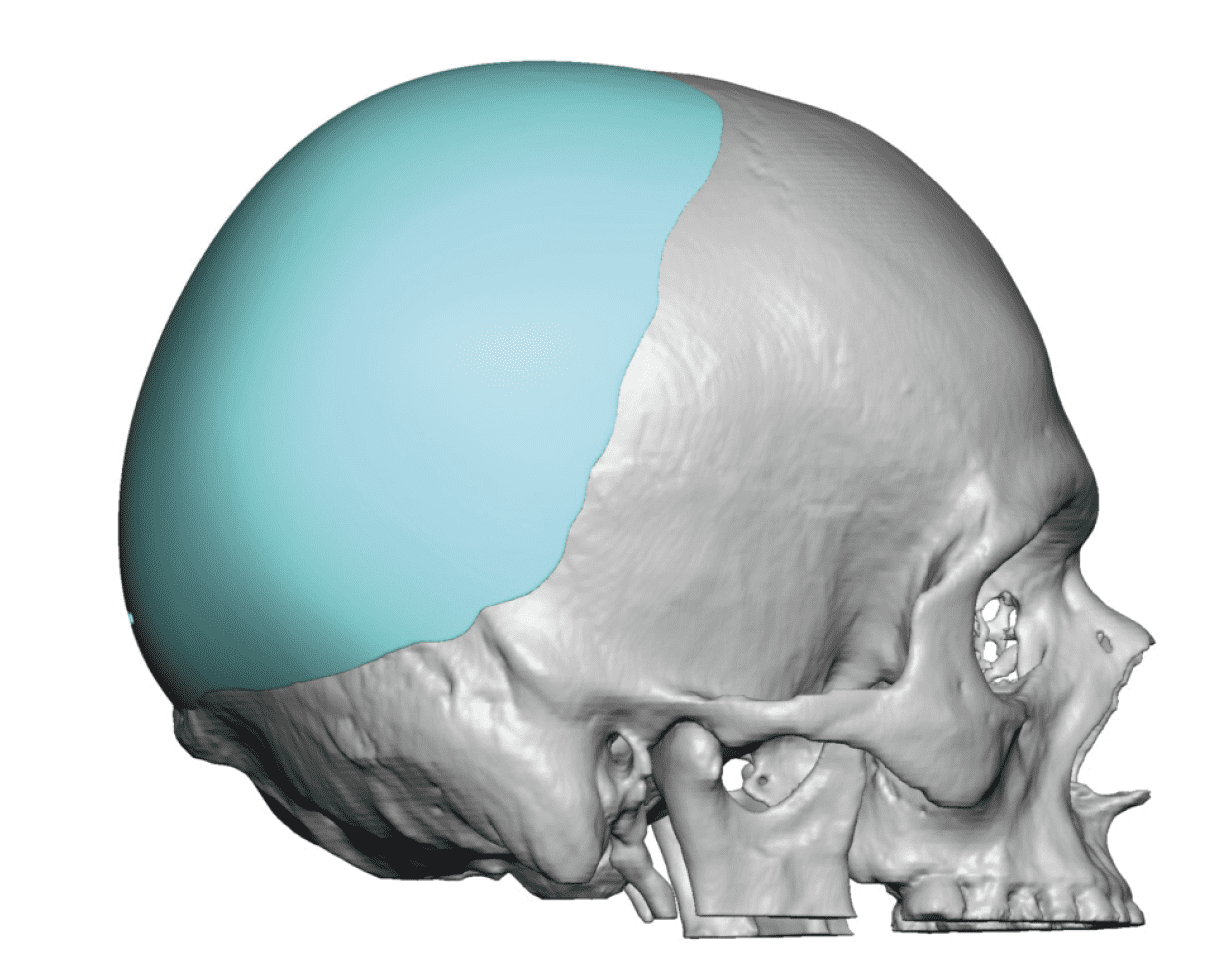

Desire to build up the flatter upper part of the back of his head.

Upper occipital skull augmentation using a custom skull implant.

Desire to build up the flatter upper part of the back of his head.

Upper occipital skull augmentation using a custom skull implant.